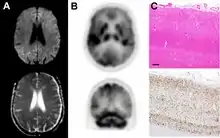

Histopathology

Testing of tissue remains the most definitive way of confirming the diagnosis of CJD, although it must be recognized that even biopsy is not always conclusive.[51]

In one-third of people with sporadic CJD, deposits of "prion protein (scrapie)", PrPSc, can be found in the skeletal muscle and/or the spleen.[52] Diagnosis of vCJD can be supported by biopsy of the tonsils, which harbor significant amounts of PrPSc; however, biopsy of brain tissue is the definitive diagnostic test for all other forms of prion disease. Due to its invasiveness, biopsy will not be done if clinical suspicion is sufficiently high or low. A negative biopsy does not rule out CJD, since it may predominate in a specific part of the brain.[53]

The classic histologic appearance is spongiform change in the gray matter: the presence of many round vacuoles from one to 50 micrometers in the neuropil, in all six cortical layers in the cerebral cortex or with diffuse involvement of the cerebellar molecular layer.[54] These vacuoles appear glassy or eosinophilic and may coalesce. Neuronal loss and gliosis are also seen.[55] Plaques of amyloid-like material can be seen in the neocortex in some cases of CJD.[56]

However, extra-neuronal vacuolization can also be seen in other disease states. Diffuse cortical vacuolization occurs in Alzheimer's disease, and superficial cortical vacuolization occurs in ischemia and frontotemporal dementia. These vacuoles appear clear and punched-out. Larger vacuoles encircling neurons, vessels, and glia are a possible processing artifact.[53]